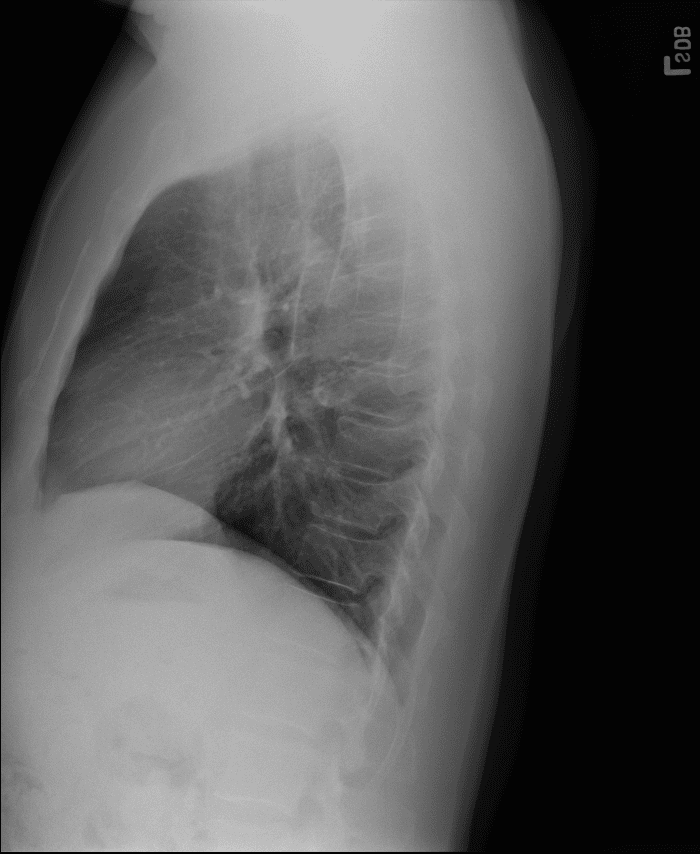

Practice Cases